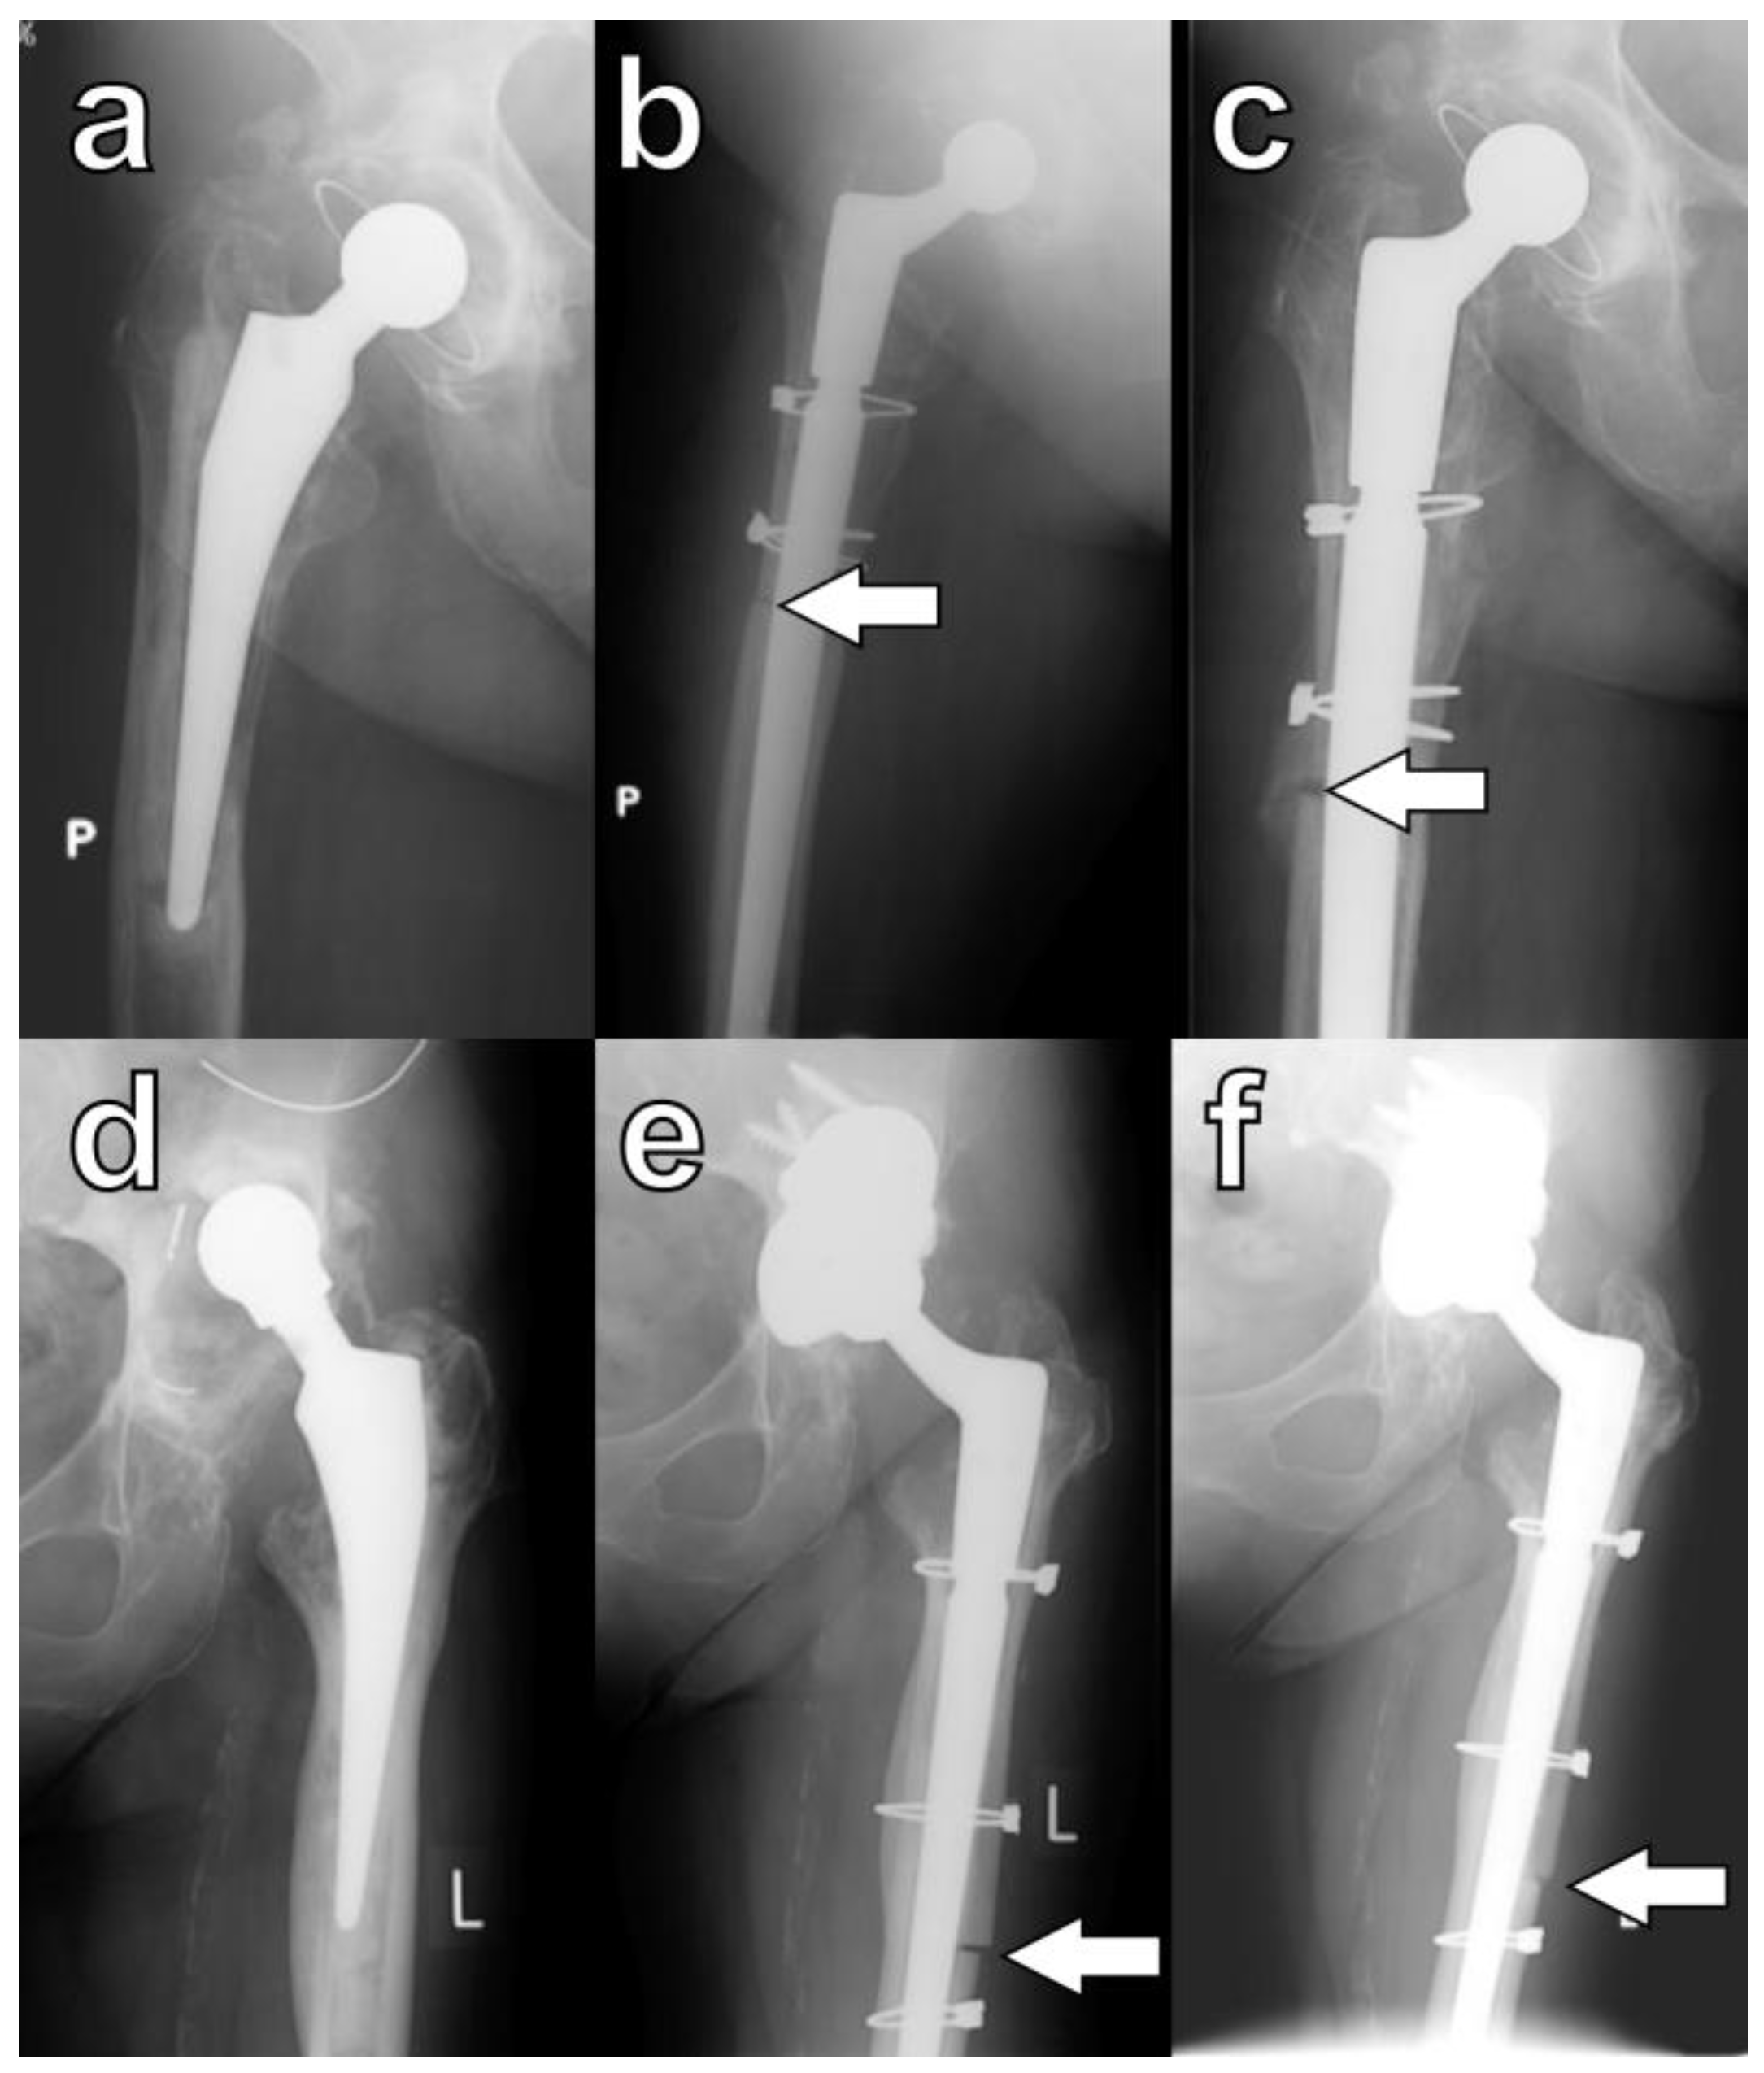

In this study, during the final evaluation, a lack of osteotomy union on any of the orthogonal radiographs was observed in four hips (9.5%). However, this phenomenon was not associated with decreased functional outcomes, and none of these patients required revision procedures (Figure 5a–c). In five hips, despite careful surgical techniques, large cortical bone fragments denuded of muscle were inadvertently broken off intraoperatively. Each of these devascularized fragments was subsequently attached to the femoral stem, and in all cases, osseointegration was observed (Figure 5d–f).

Figure 5.

Specific cases of ETO healing: lack of bone formation within the osteotomy (a) pre-op, (b) at six months, and (c) at twenty-four months. Osseointegration of a devascularized bone fragment: (d) pre-op, (e) at three months, and (f) at six months; arrows indicate osteotomy sites. P is right side, and L is left side.